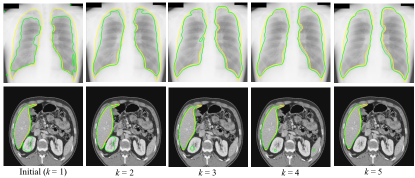

To validate our noise-robust iterative method to learn from noisy pseudo labels obtained by , we compared the following variants: 1) U-Net (baseline) that learns from the pseudo labels using a standard Dice loss without considering the existence of noise; 2) U-Net (MAE) that uses MAE loss [38] for training; 3) U-Net () that uses generalized cross entropy loss [40] for training; 4) U-Net trained with Dice loss from samples selected by our LQSS, which is referred to as U-Net (LQSS). These four methods only train the model once without iterative training, and were further compared with: 5) U-Net (LQSS + IT) that refers to U-Net (LQSS) followed by iterative training with Dice loss; and 6) U-Net (LQSS + IT + wDice) that refers to U-Net (LQSS) followed by iterative training with our noise-weighted Dice loss. For the last two variants, the round number determined by the validation set was 3 and 4 for optic disc segmentation and fetal head segmentation, respectively. The quantitative evaluation results are shown in Table 4, which shows that LQSS obtained better performance than the baseline, and using iterative training and noise-weighted Dice loss further improves the segmentation accuracy. Fig. 8 shows that our LQSS is able to reject low-quality pseudo labels with some noise, e.g., over segmentation with false positives. Note that in Fig. 8(a), the second rejected case of has a higher contrast than the first accepted case, which shows our LQSS does not tend to only select easy samples. Fig. 6 demonstrates the refinement of pseudo labels at different rounds of training stage. Fig. 9 shows the performance at different rounds of our iterative method to learn from noisy pseudo labels obtained by . It shows that the performance increased at the beginning and reached a plateau after two rounds for optic disc and three rounds for fetal head, and that noise-weighted Dice loss is better than Dice loss during the iterative training. We compared our ellipse-based shape prior with circle-based shape prior to obtain the pseudo labels, and they are denoted as U-Net (baseline) and U-Net (baseline)∘, respectively. Results in Table 4 show that modeling optic disc and fetal head as ellipses largely outperform modeling as circles.

To validate our noise-robust iterative method to learn from noisy pseudo labels obtained by our generator , we first compared the following variants: 1) U-Net (baseline) that learns from the pseudo labels using a standard Dice loss without considering the existence of noise; 2) U-Net trained with Dice loss from samples selected by our LQSS, which is referred to as U-Net (LQSS). These two methods only train the model once without iterative training, and were further compared with: 3) U-Net (LQSS + IT) that refers to U-Net (LQSS) followed by iterative training with Dice loss (five rounds); and 4) U-Net (LQSS + IT + wDice) that refers to U-Net (LQSS) followed by iterative training with our noise-weighted Dice loss (five rounds). The quantitative evaluation results are shown in Table 6. It can be observed that the LQSS obtained better performance than the baseline, and using iterative training and noise-weighted Dice loss can further improve the segmentation accuracy. As shown in Table 6, the iterative training with our noise-weighted Dice loss improved the segmentation Dice score from 0.907 to 0.926 for the lung, and from 0.908 to 0.933 for the liver, respectively. The results show that iteration process is important for learning from noisy pseudo labels. Fig. 13 demonstrates the pseudo labels refined at different rounds of training stage, and it can be observed that the quality of pseudo labels are gradually improved during the training rounds. Fig. 15 shows the performance of iterative training on the testing set. It demonstrates that the performance increased at the beginning and reached a plateau after four rounds, and also shows that noise-weighted Dice loss is better than Dice loss during the iterative training.